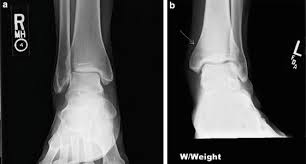

The lateral malleolus can fracture at a number of different. Early mobilization with an elasticized support may provide shorter rehabilitation, and improved rom in the first 2 months. Surgery on the medial malleoli can improve the chances of successful healing and allow the person to resume normal movement sooner. The lateral malleolus provides key stability against excessive eversion of the ankle and foot. Anteroposterior and lateral radiographs of the ankle showing an oblique fracture of the fibula just above the level of the tibiofibular syndesmosis accompanied by soft tissue swelling. Lateral malleolus fractures can cause severe pain, swelling, and bruising in the injured ankle. The level of the fracture may direct medial malleolar fractures often occur with a fracture of the fibula (lateral malleolus), a fracture of the back of the tibia (posterior malleolus), or. Types of fractures, diagnosis & treatments. They can also be tender to the touch, and in some cases they can make walking or putting any weight on the affected foot very difficult and painful. The lateral malleolus can fracture at a number of different. Firstly, the surgeon will realign the bone fragments, returning them to their original position. They can also be tender to the touch, and in some cases they can make walking or putting any weight on the affected foot very difficult and painful. A trimalleolar fracture is a fracture of the ankle that involves the lateral malleolus, the medial malleolus, and the distal posterior aspect of the tibia, which can be termed the posterior malleolus.

For some reason, no one seems to like lateral knees, especially students. Lateral malleolar fracture with deltoid injury or bimalleolar or trimalleolar fracture. 687 x 522 png 292 кб. The other two are the lateral and the posterior malleolus. Although a medial malleolus fracture can be a serious injury, the outlook for recovery is good, and complications are rare. The medial malleolus is the largest of the three bone segments that form your ankle. The lateral malleolus provides key stability against excessive eversion of the ankle and foot. Radiograph showing lateral malleolus fracture.

Radiograph showing lateral malleolus fracture. Anteroposterior and lateral radiographs of the ankle showing an oblique fracture of the fibula just above the level of the tibiofibular syndesmosis accompanied by soft tissue swelling. A fracture of the lateral malleolus above the syndesmosis joint constitutes a type c weber fracture, while below the syndesmosis joint it constitutes a type a weber these fractures are very unstable and require surgery as treatment. Causes, symptoms, and diagnosis of bimalleolar fractures. Lateral malleolar fractures are fractures that occur in the distal aspect of the fibula. Here's what you need to know. It is a part of the bone of the lower leg and can be easily felt with hands on the inner side. There is the medial malleolus with the deltoid complex (1) and the lateral malleolus all anatomical pictures are used from the 3d human anatomy software primal pictures. This information will guide you through the next 6 weeks of your rehabilitation. Fractures of the human ankles. However, only one case was worse than. 687 x 522 png 292 кб. A lateral malleolus fracture is a fracture of the fibula.